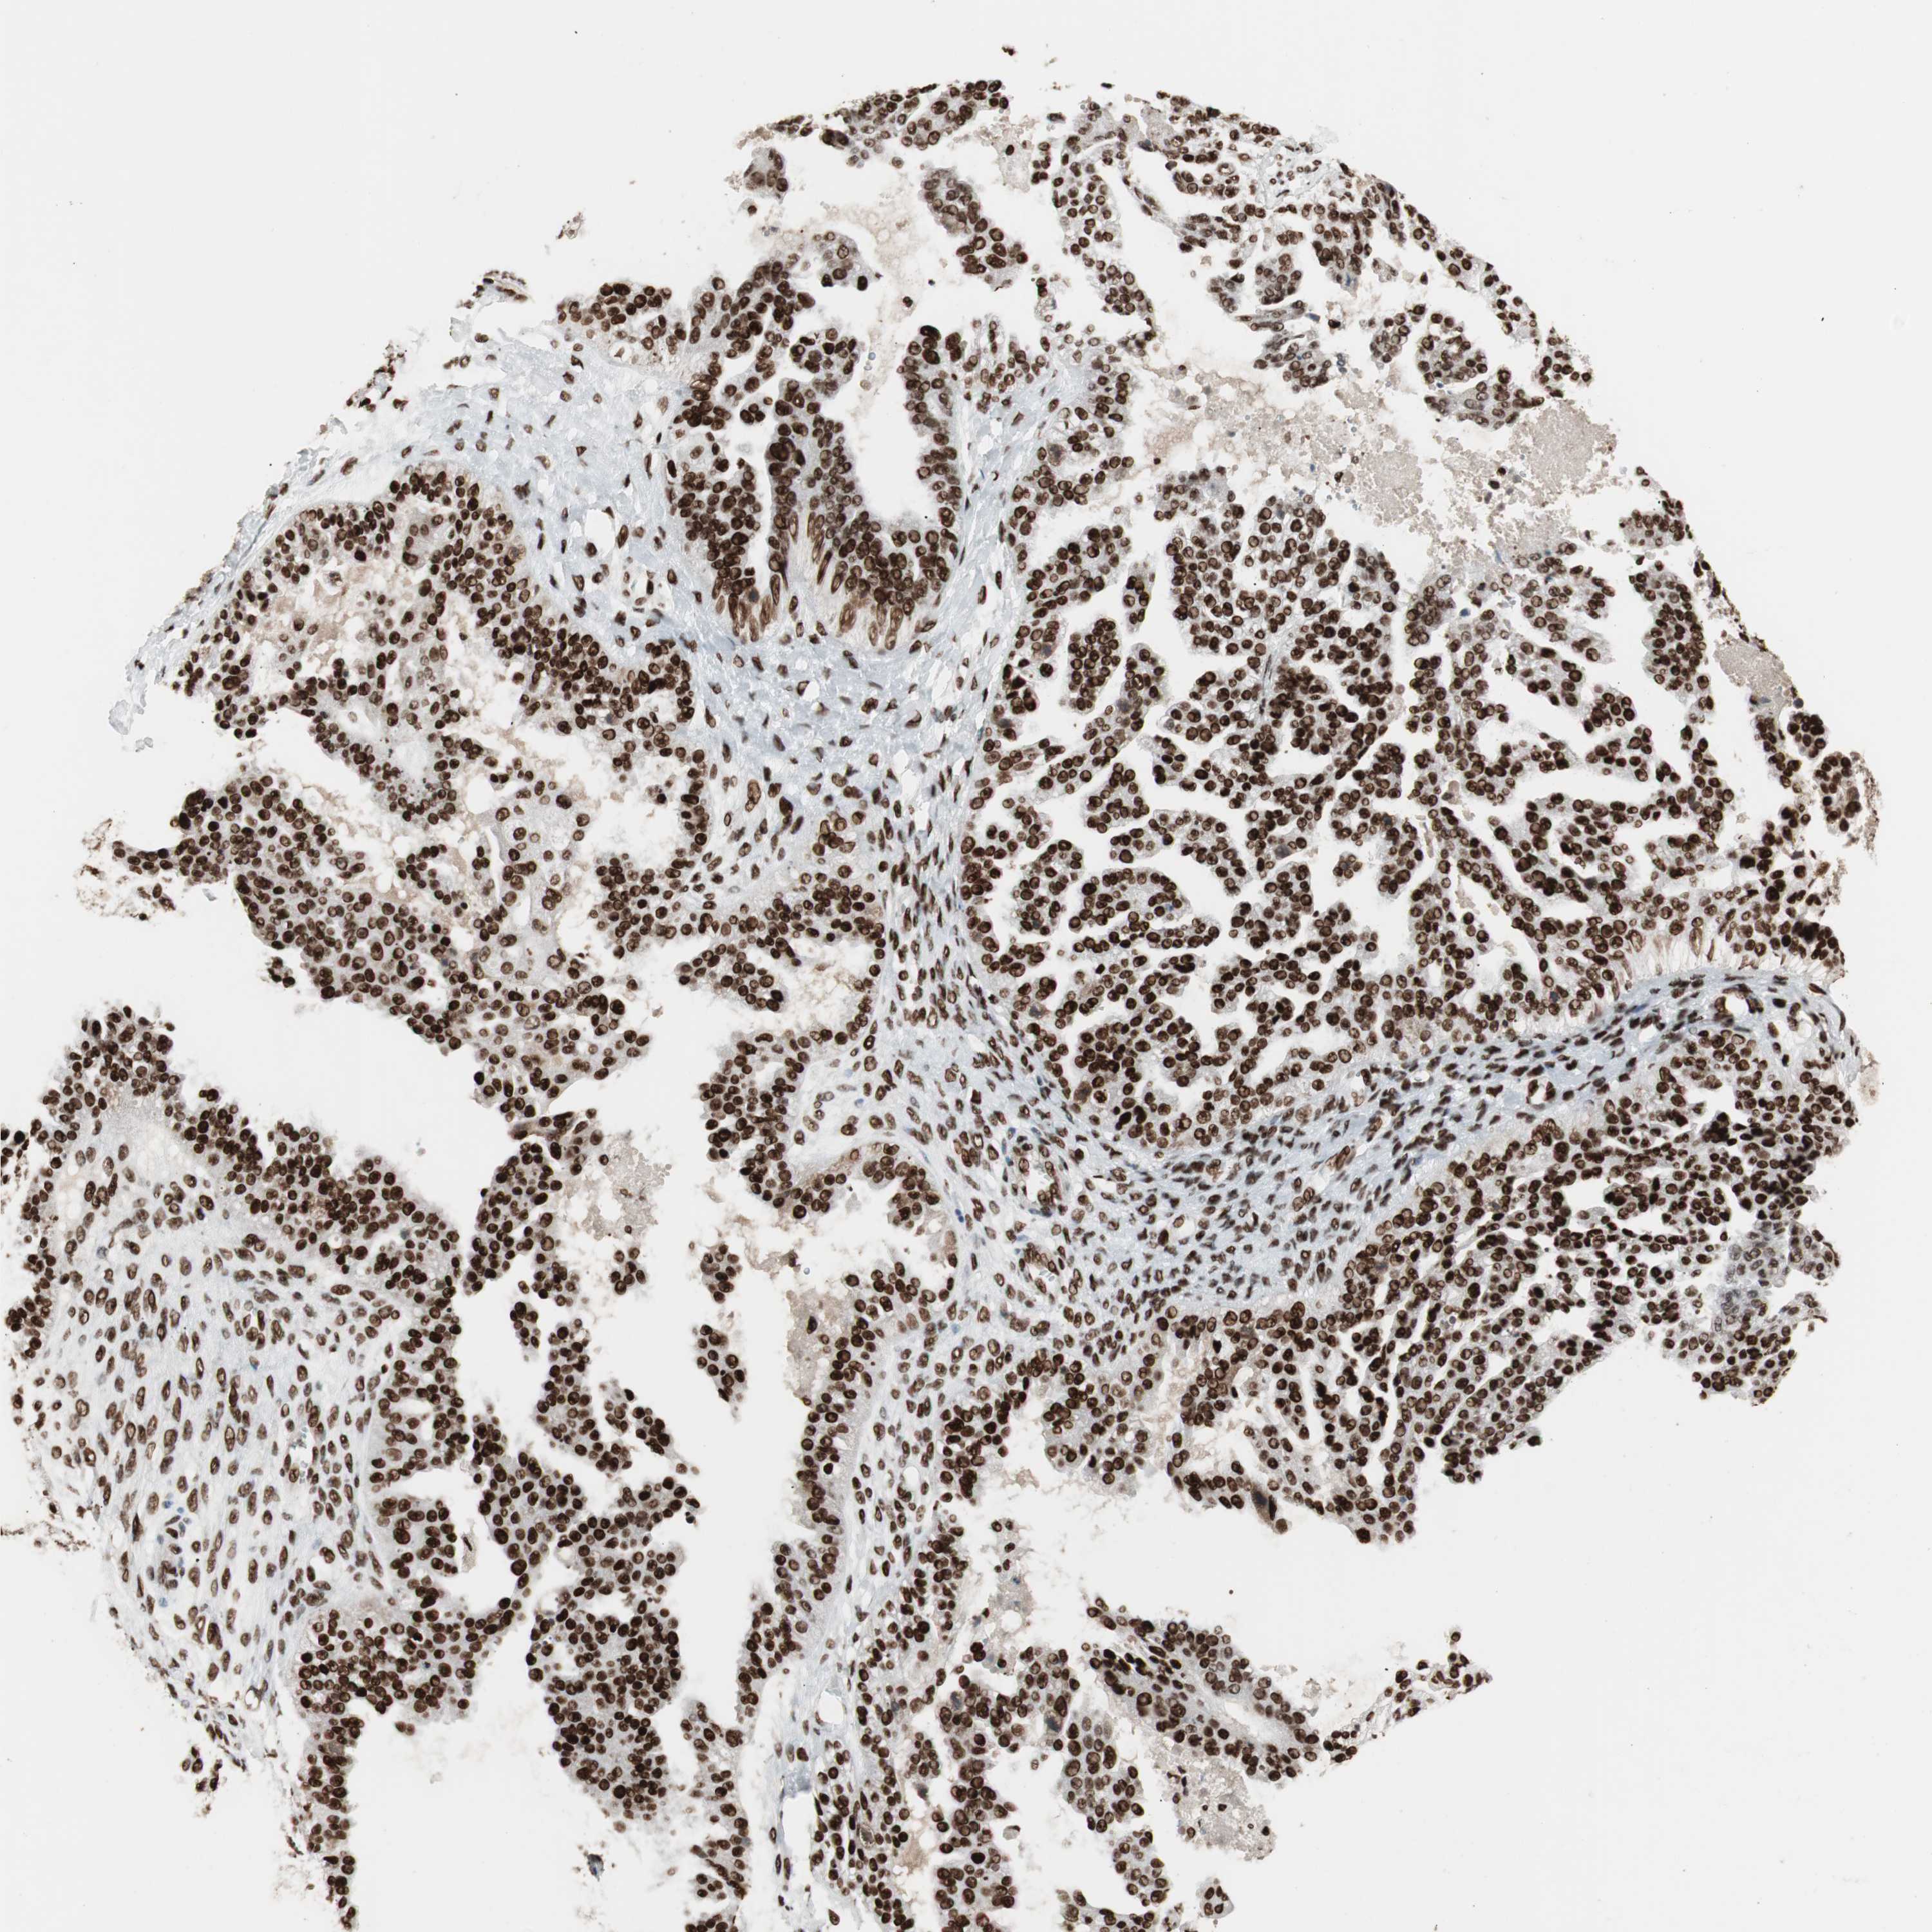

OVARIAN CANCER - Protein expressioni

A mouse-over function shows sample information and annotation data. Click on an image to view it in a full screen mode. Samples can be filtered based on level of antibody staining by selecting one or several of the following categories: high, medium, low and not detected. The assay and annotation is described here.

Note that samples used for immunohistochemistry by the Human Protein Atlas do not correspond to samples in the TCGA dataset.

Antibody stainingi

Antibody staining in the annotated cell types in the current human tissue is reported as not detected, low, medium, or high, based on conventional immunohistochemistry profiling in selected tissues. This score is based on the combination of the staining intensity and fraction of stained cells.

Each image is clickable and will lead to virtual microscopy that enables deeper exploration of all samples and also displays staining intensity scores, fraction scores and subcellular localization as well as patient and tissue information for each sample.

Antibody HPA012510

Antibody CAB008388

Staining

High

Medium

Low

Not detected

Intensity

Strong

Moderate

Weak

Negative

Quantity

>75%

75%-25%

<25%

None

Location

Nuclear

Cytoplasmic/membranous

Cytoplasmic/membranous,nuclear

Cystadenocarcinoma, serous, NOS

Carcinoma, endometroid

Cystadenocarcinoma, mucinous, NOS

Carcinoma, NOS